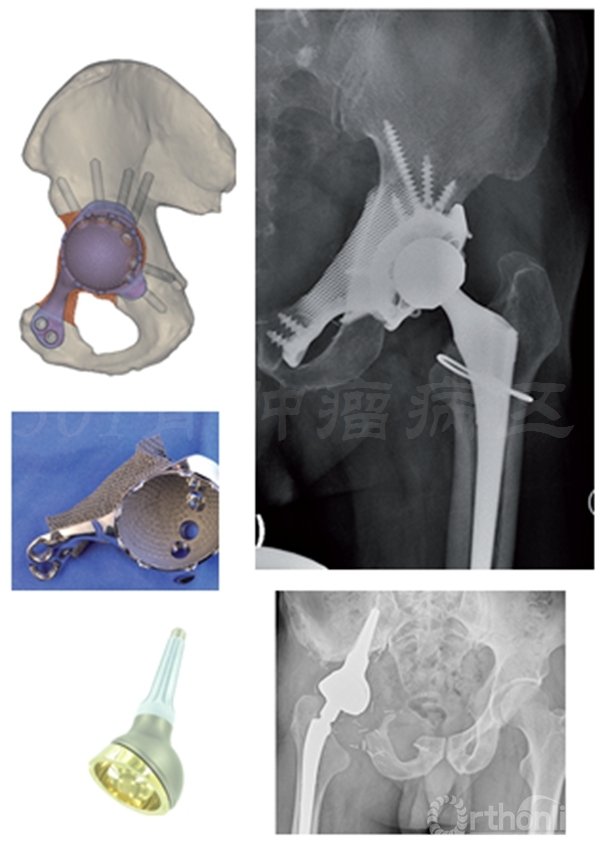

髋臼肿瘤多为髂骨或耻坐骨连同髋臼同时受到肿瘤的破坏。累及髋臼的骨盆肿瘤切除、重建是具有挑战的手术,各类假体置换是主要治疗手段,主要包括组配假体,个体化定制假体,3D打印假体,“冰淇淋杯”假体;复合或不复合异体骨移植等。

股骨头旷置术